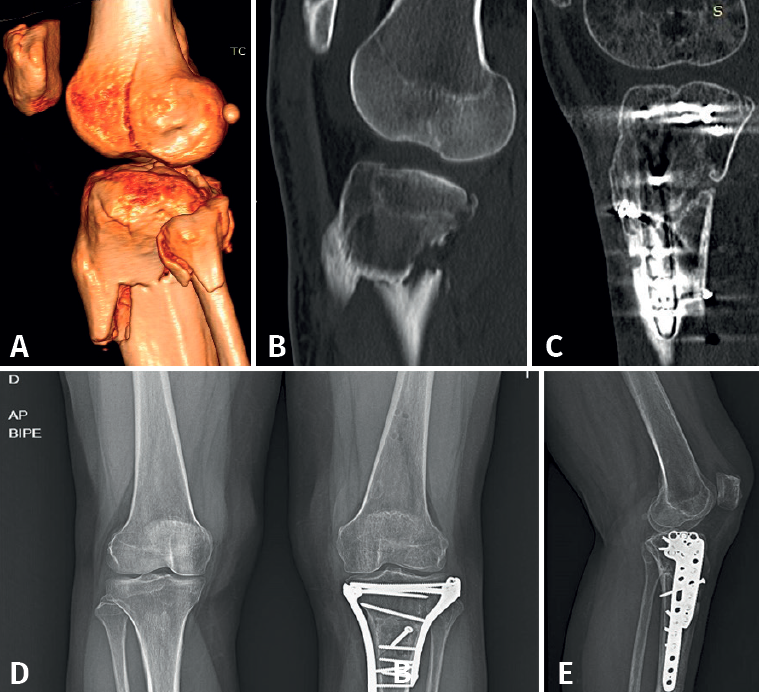

retla.05210.fs2208015-figura3.png

Figura 3. Fractura osteocondral en el cóndilo femoral externo de la rodilla izquierda de una mujer de 52 años en el contexto de una rodilla traumática con fractura multifragmentaria proximal de la tibia. A y B: imágenes de la tomografía computarizada (TC) preoperatoria; C: TC de control donde se aprecia la fractura osteocondral de fémur in situ con un mínimo escalón; D y E: radiografías en carga al alta de la paciente.